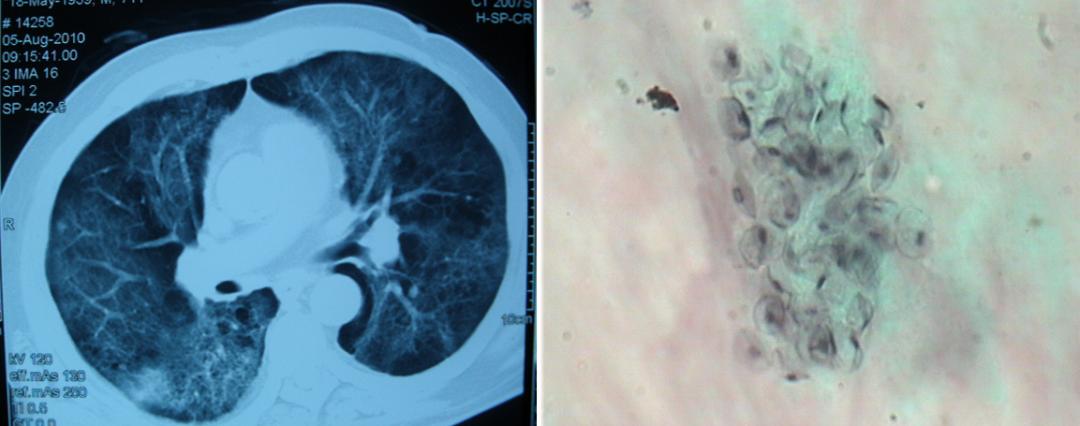

影像可见患者右下肺有较大的实变:

胸水是血性的,我们下了决心去穿刺,肺穿刺组织培养48小时发现根毛霉,病理也看到了丝状真菌: